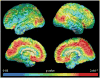

Findings: We enrolled a cohort of 11 symptomatic individuals, 19 presymptomatic mutation carriers, and 20 asymptomatic non-carriers, ranging in age from 20 to 56 years. There was greater florbetapir binding in asymptomatic PSEN1 E280A mutation carriers than in age matched non-carriers. Fibrillar Aβ began to accumulate in PSEN 1E280A mutation carriers at a mean age of 28·2 years (95% CI 27·3-33·4), about 16 years and 21 years before the predicted median ages at mild cognitive impairment and dementia onset, respectively. (18)F florbetapir binding rose steeply over the next 9·4 years and plateaued at a mean age of 37·6 years (95% CI 35·3-40·2), about 6 and 11 years before the expected respective median ages at mild cognitive impairment and dementia onset. Prominent florbetapir binding was seen in the anterior and posterior cingulate, precuneus, and parietotemporal and frontal grey matter, as well as in the basal ganglia. Binding in the basal ganglia was not seen earlier or more prominently than in other regions.